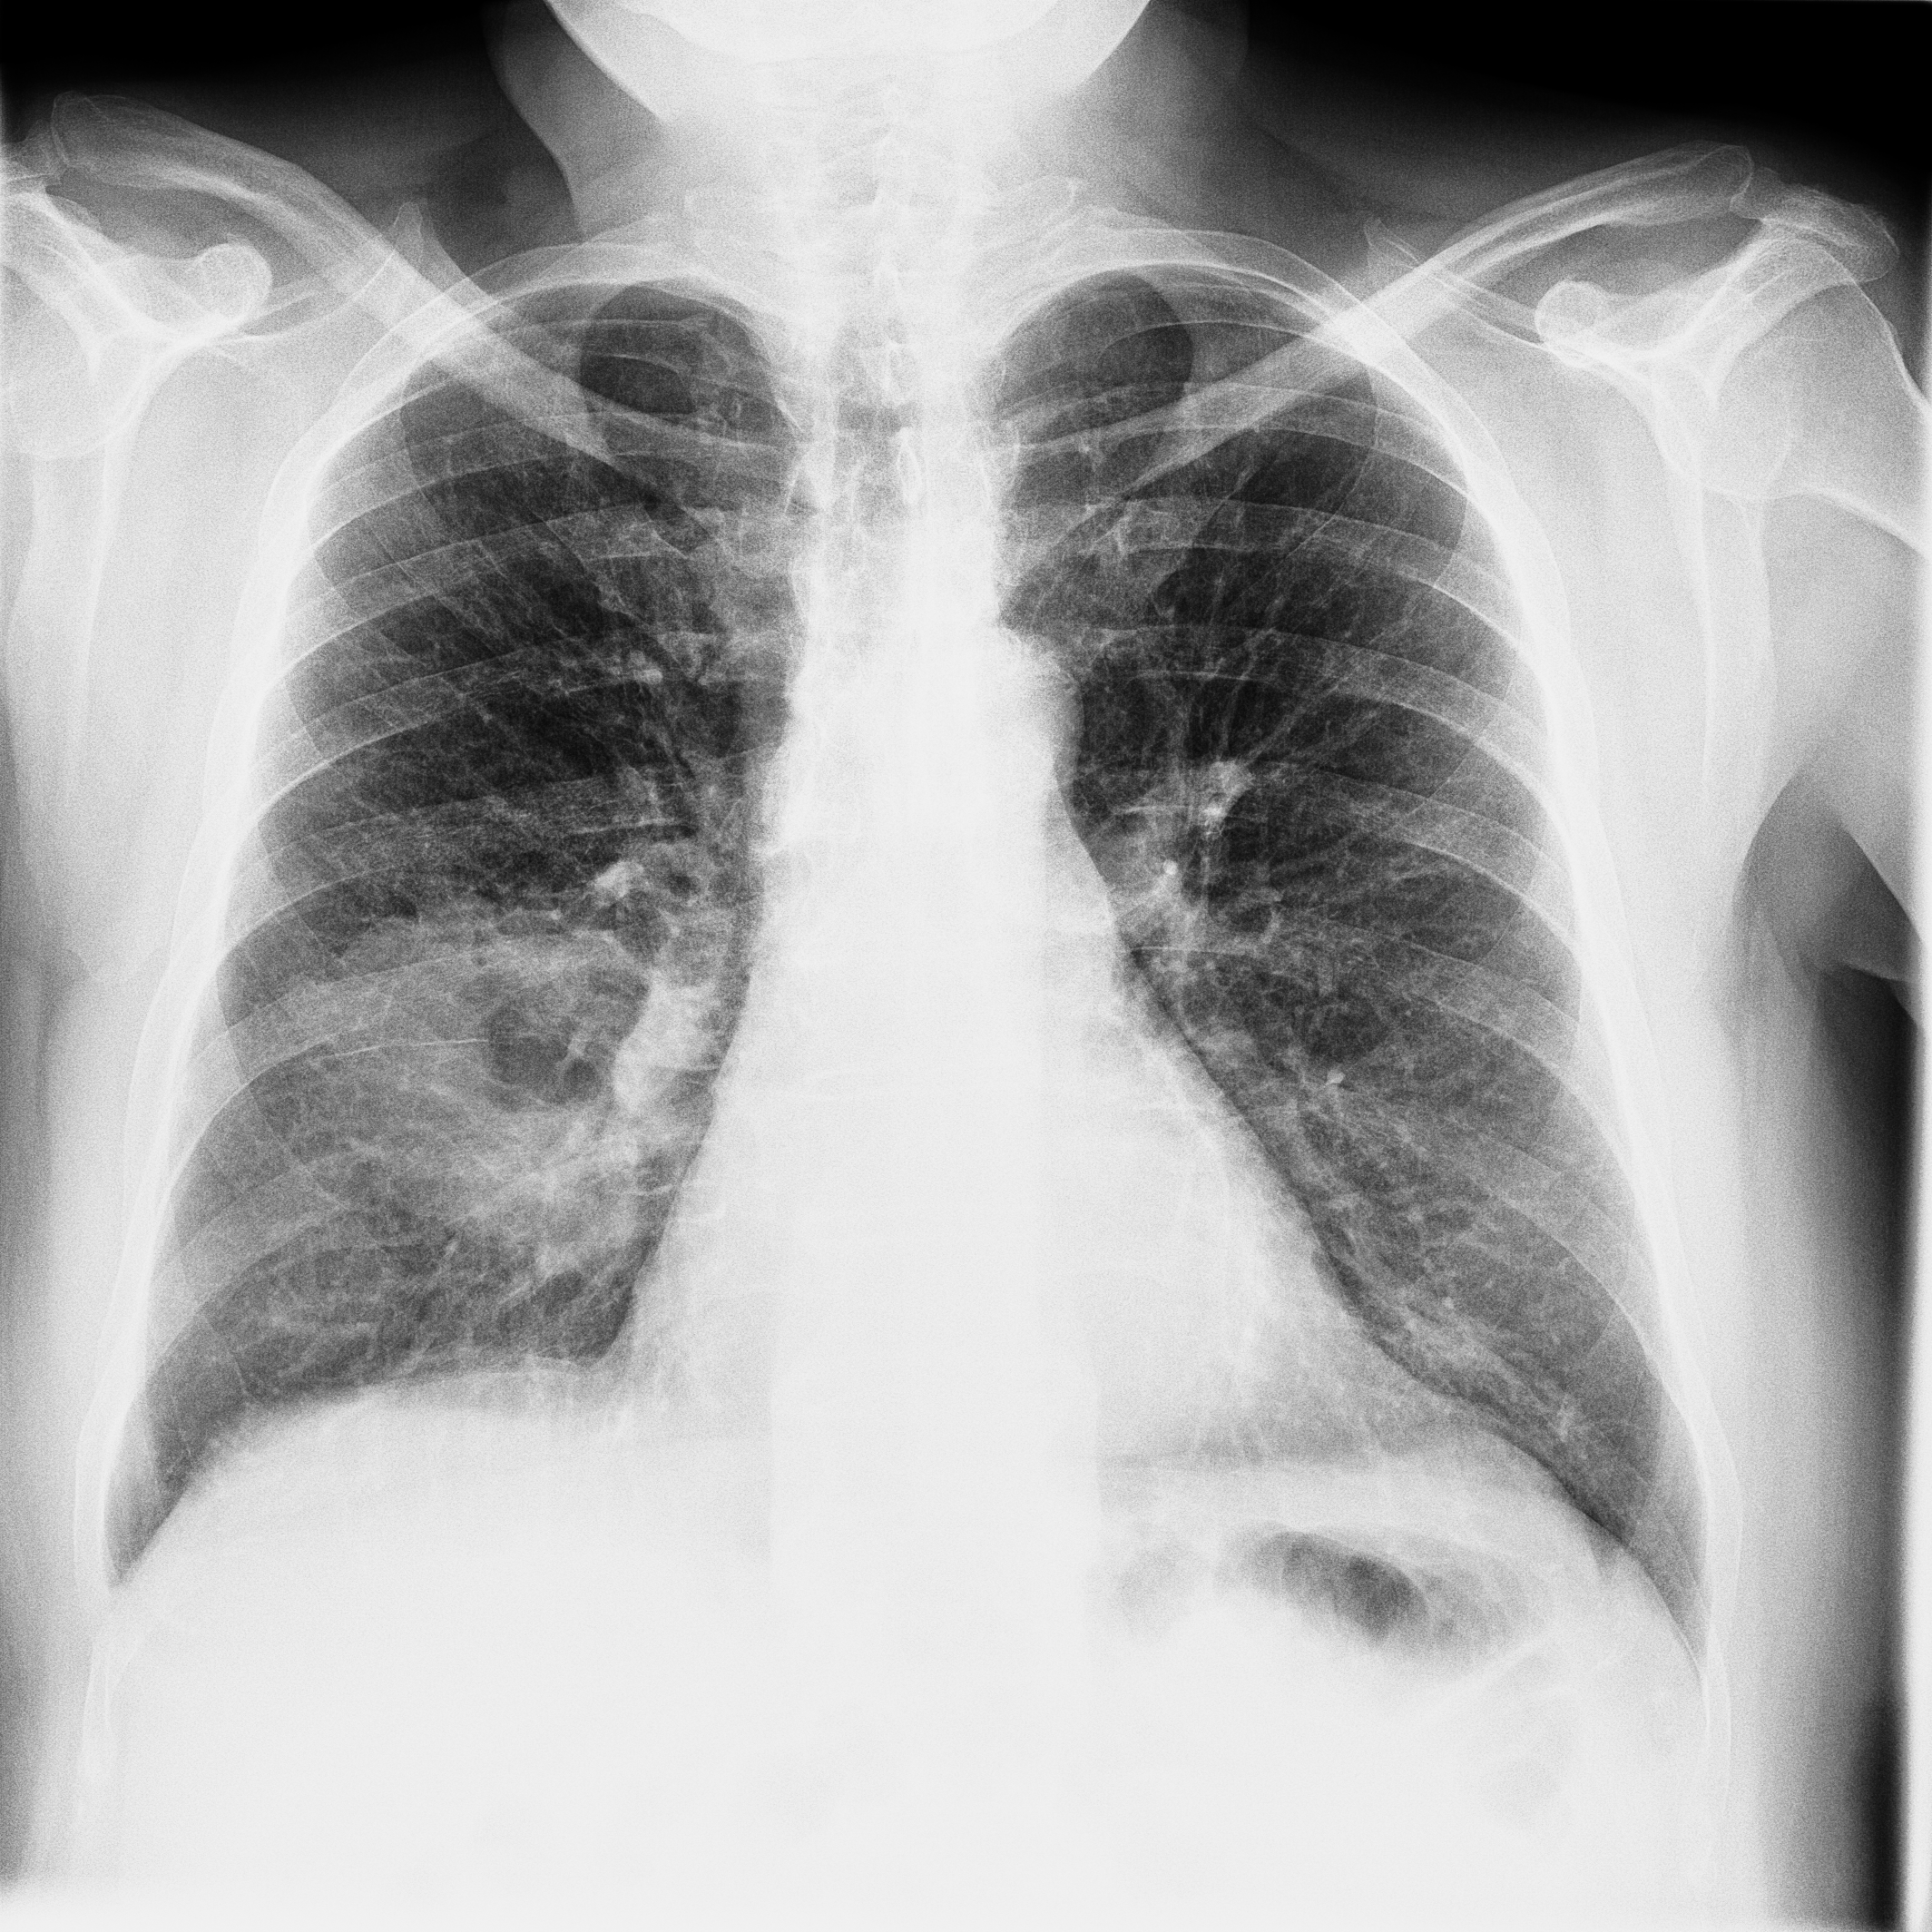

3.1.3 Example 2: data driven reconstruction methods in lung CT screening

There is sufficient evidence that screening for certain tumours using CT images may improve prognosis of cancer survivability (citep \@BBN(Boiselle, 2013)). As mentioned above, in order to gain better image quality with less X-ray dose, many enhanced regularization techniques with integrated machine learning steps have been suggested for CT reconstruction, and in a full reference setting they are commonly evaluated by applying PSNR and SSIM, see e.g. (citep \@BBN(Adler and Öktem, 2018; Hendriksen, Pelt, and Batenburg, 2020; Unal, Ertas, and Yildirim, 2021)). As CT images are generally taken to perform a clinical task, they are not the final step of a medical process but often the initial one. Therefore the definition of what makes a good image heavily depends on the task in hand, and for prognosis related cancer the identification of tumours is of upmost importance.

In on-going research on photon counting detector types and screening procedures for lung cancer (EPSCR grant: EP/W004445/1) an experiment was conducted testing enhanced reconstruction algorithms. Simulations using less than 10% of a clinical X-ray dose were performed to investigate if data-driven methods could sufficiently enhance the images to clearly see the tumours in the lungs while providing very low amount of dosage to the patients. The corresponding data was a CT-dose simulation, using images from the open LIDC-IDRI dataset (citep \@BBN(Armato et al., 2011)) as references, as well as simulated and reconstructed images with in-house software. Figure 3 shows the results of the experiment. We show the reference image used as basis for the simulation, together with five different reconstruction algorithms. The first is an iterative solver, a gradient descend algorithm with TV minimization (citep \@BBN(Sidky et al., 2012)) and (c)-(f) correspond to machine learning methods: FBPConvnet is a denoising algorithm that cleans the bad image (citep \@BBN(Jin et al., 2017)), LPD is an iterative unrolled method that combines traditional solvers with machine learning (citep \@BBN(Adler and Öktem, 2018)), Noise2Inverse is a self-supervised learning method (i.e. does not require ground truth data) (citep \@BBN(Hendriksen et al., 2020)) and ItNet is another iterative unrolled method, the best performing winner of the AAPM DL-Sparse-View CT challenge (citep \@BBN(Genzel, Macdonald, and März, 2021)). ItNet is also judged here as the best result according to PSNR, SSIM and LPIPS.

Refer to caption

(a) Reference

(b) (27.6, 0.70, 0.37)

(c) (31.9, 0.73, 0.29)

(d) (32.5, 0.84, 0.19)

(e) (32.5,0.77, 0.20)

(f) (33.0, 0.89, 0.12)

Figure 3: Reference image (a) and outputs of different reconstruction methods (b)-(f) applied to dose simulated data. PSNR/SSIM/LPIPS are unable to identify the best reconstruction (c), where also the tumour is visualized well.

FR-IQA mismatches

This experiment was performed to evaluate the quality of different kinds of CT reconstruction, and especially the lung tumour detection capabilities thereof. The best result according to the chosen IQA measures is given by ItNet in Figure 3(f), which performs visually poorly. Not only the tumour (zoomed in white circle) is significantly less visible in the reconstruction, but ItNet also produces structures in the lung that are different than the ones in the reference image; it blurs and lengthens much of the soft tissue present in the lungs and it also created structure from noise in some places. Moreover, the image is overly smooth. Comparing the other reconstruction algorithms, it seems that FBPConvnet Figure 3(c) is the one performing best at preserving the shape of the lung nodule, even when the resulting image contains enhanced pixel-level noise.

We can see here that the qualitative findings strongly contradict the numbers provided by the selected measures. The reconstruction of ItNet, Figure 3(f), is outperforming the other reconstructions in regards of the measures, and the qualitative winner FBPConvnet, Figure 3(c), is judged as second worst by the same measures. This experiment suggests that the discussed measures are not a good choice for that kind of CT reconstruction applications and are yielding misleading results.

While pixel-independent random noise may be a worse effect in a natural image than a slightly oversmooth reconstruction, this is not true in CT images, where small structures may disappear if smoothing is promoted against edge preservation. In iterative reconstruction algorithms such choices are explicitly made by choosing the prior appropriately, in data-driven models the researcher has limited control on the type of implicit priors the algorithm learns from the data, i.e. model builders do not know what the algorithms chooses to learn from the ground truth. In these cases appropriate evaluation would therefore be even more important to ensure quality. If this is followed by a blind evaluation using non-appropriate metrics, the promotion of less desirable images can happen, chosen by an implicit assumption on the metric rather than the actual goal of the task.